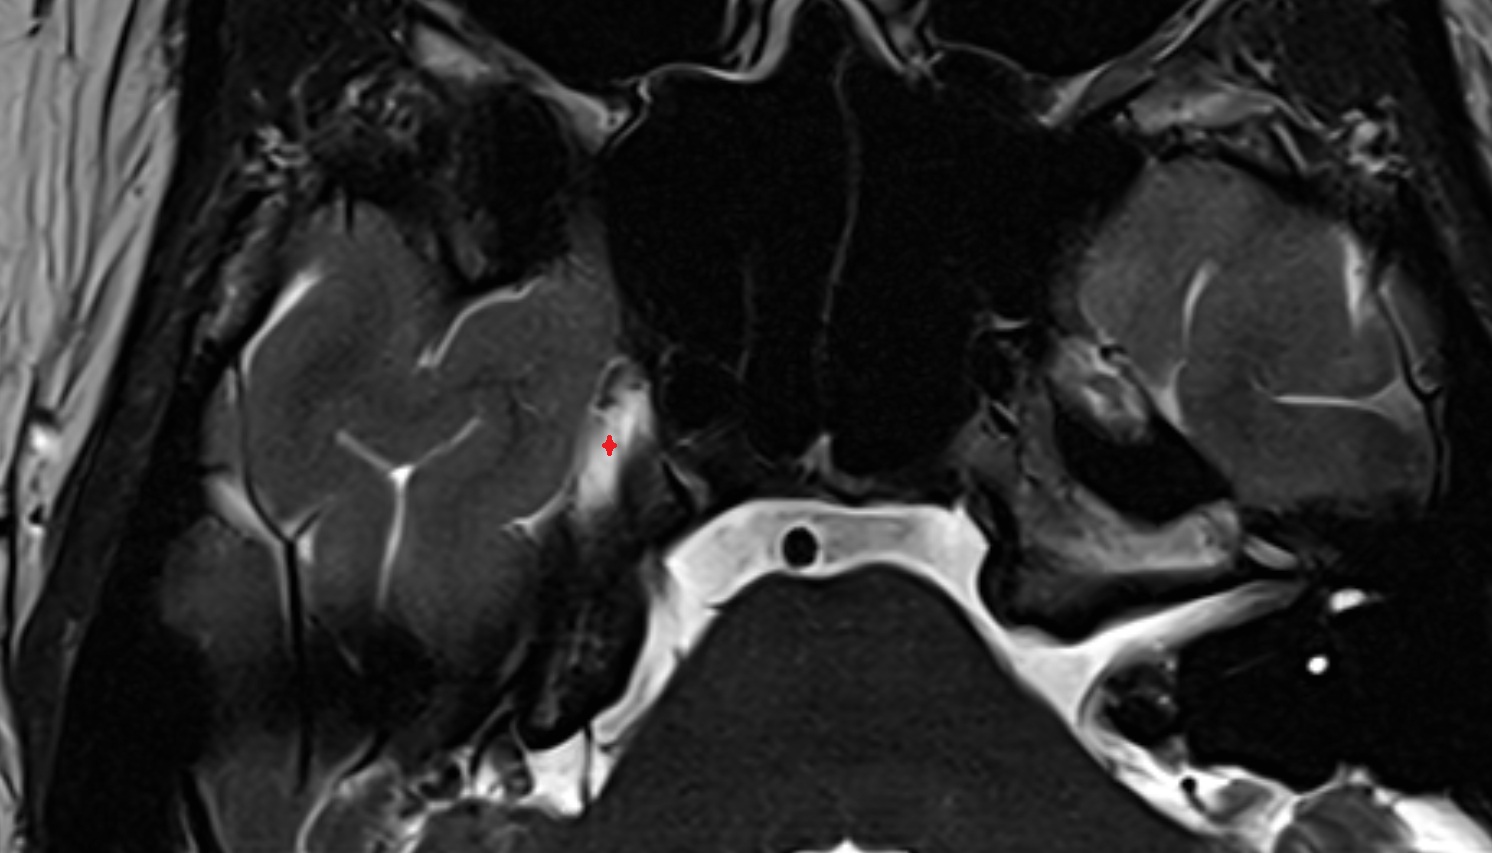

Meckel’s cave (Trigeminal cave) mri axial image -img-00000-00000

T2-weighted images:

• The cave is hyperintense due to CSF, creating a bright background that clearly outlines the ganglion.

• Nerve fibers and lesions may be distinguished by intermediate or heterogeneous signal intensity.

• Useful for detecting edema, cysts, or tumors involving the trigeminal nerve or ganglion.